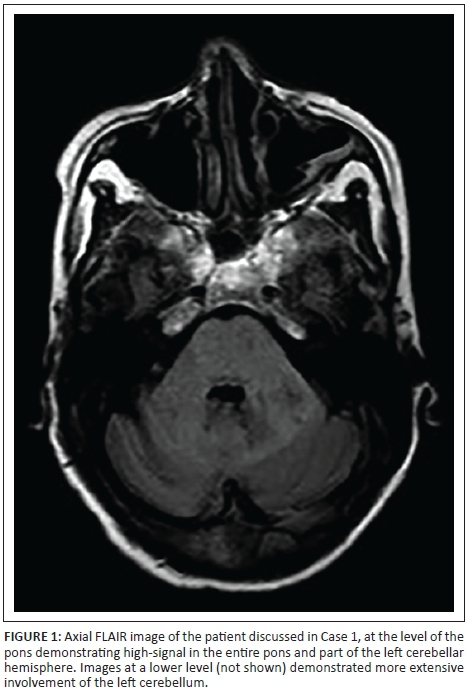

A 34-year-old HIV-positive woman with a CD4 cell count of 24 cells/µL and not on HAART, presented with confusion and ataxia. On examination, she had nystagmus, severe dysarthria and a broad-based gait. She had a history of alcohol abuse, and the possibility of Wernicke encephalopathy was considered, which was treated with thiamine. MRI was requested, which showed high-signal on T2-weighted and FLAIR sequences in the left cerebellar hemisphere, pons and midbrain (Figure 1). There was no restricted diffusion, no associated mass effect nor enhancement on post contrast imaging. The CSF yielded no growth, and the JC virus PCR was positive. The patient deteriorated in the ward and subsequently demised.